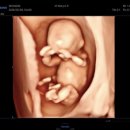

참고 러브 다이브* 하듯 코에 힘주며 열었다. 설거지도 못하고 빨래도 못해서 남편이 한창 고생했던 때 다음에는 1차 기형아 검사를 한다고 해서 괜히 긴장...2주 전보다도 훨씬 사람처럼 생겼고 너무 귀여웠다 흐규흐규 나는 이 아이 덕분에 입덧이라는 신세계를 경험 중인데 막상 키가 5.77cm 밖에 되지...